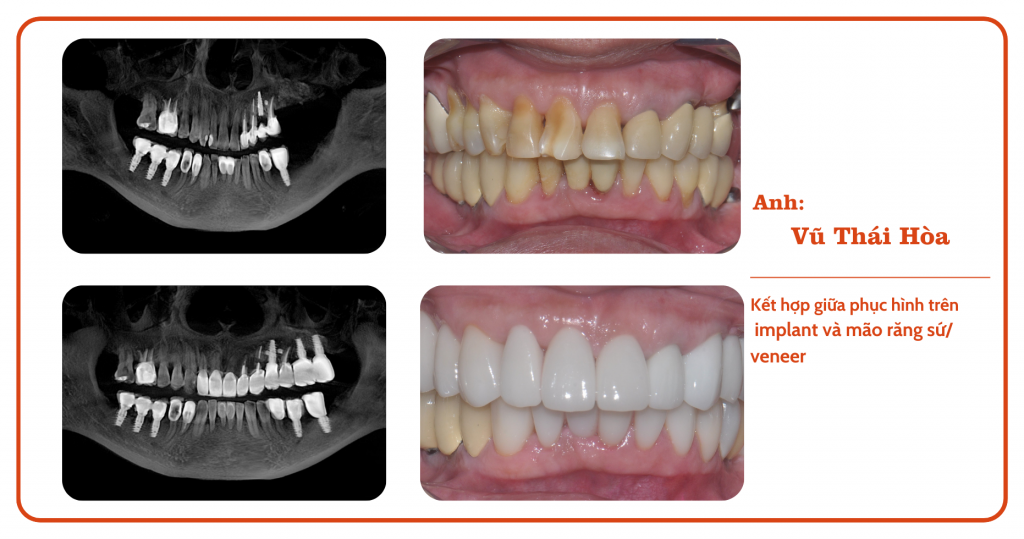

Tình trạng răng miệng của anh Hòa khá phức tạp: mất một vài răng lâu năm, các răng còn lại thì bị sứt mẻ, ố vàng và mọc không đều. Anh đã tìm hiểu nhiều phương pháp thẩm mỹ răng nhưng vẫn chưa tìm được giải pháp phù hợp.

Quá trình điều trị của anh Hòa diễn ra theo đúng kế hoạch và đạt được kết quả ngoài mong đợi. Các trụ Implant được cấy ghép thành công, mão răng sứ và Veneer được chế tác tỉ mỉ, phù hợp với khuôn mặt và sở thích của anh.

Sự kết hợp giữa phục hình trên Implant, mão răng sứ và Veneer đã mang lại cho anh Vũ Thái Hòa một nụ cười hoàn hảo, giúp anh tự tin hơn trong công việc và cuộc sống. Nha khoa Chez vô cùng hạnh phúc khi đã góp phần thay đổi cuộc đời anh theo hướng tích cực hơn.